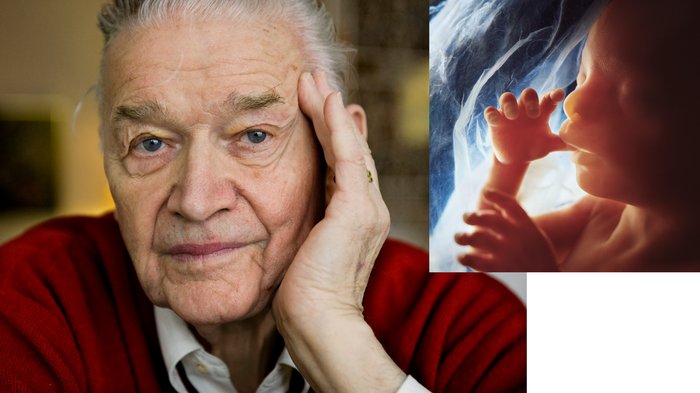

Работы знаменитого фотографа Леннарта Нильссона

Раздел: Фотопанорама